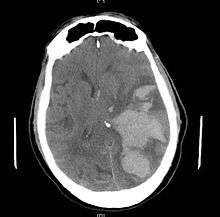

| MRI showing injury due to brain herniation | |

Treatment involves removal of the etiologic mass and decompressive craniectomy. Brain herniation can cause severe disability or death. In fact, when herniation is visible on a CT scan, the prognosis for a meaningful recovery of neurological function is poor.[2] The patient may become paralyzed on the same side as the lesion causing the pressure, or damage to parts of the brain caused by herniation may cause paralysis on the side opposite the lesion.[8] Damage to the midbrain, which contains the reticular activating network which regulates consciousness, will result in coma.[8] Damage to the cardio-respiratory centers in the medulla oblongata will cause respiratory arrest and (secondarily) cardiac arrest.[8] Current investigation is underway regarding the use of neuroprotective agents during the prolonged post-traumatic period of brain hypersensitivity associated with the syndrome.